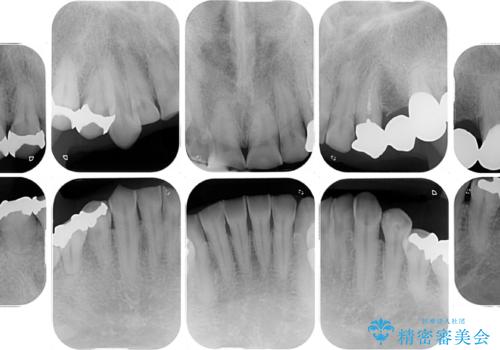

- すり減った前歯や奥歯の銀歯を気にして来院された患者様です。

骨格的な反対咬合により上顎前歯の先端が顕著にすり減っている状態でした。

奥歯の欠損が散見されており、銀歯の装着されている歯も多いため、ワイヤー矯正にて歯列を調整し、その後オールセラミッククラウンにて補綴治療を行うこととしました。

反対咬合改善には奥歯の咬み合わせをしっかりと改善させることが必要となりますが、奥歯に欠損が多いため、矯正治療が難航することが予想されます。